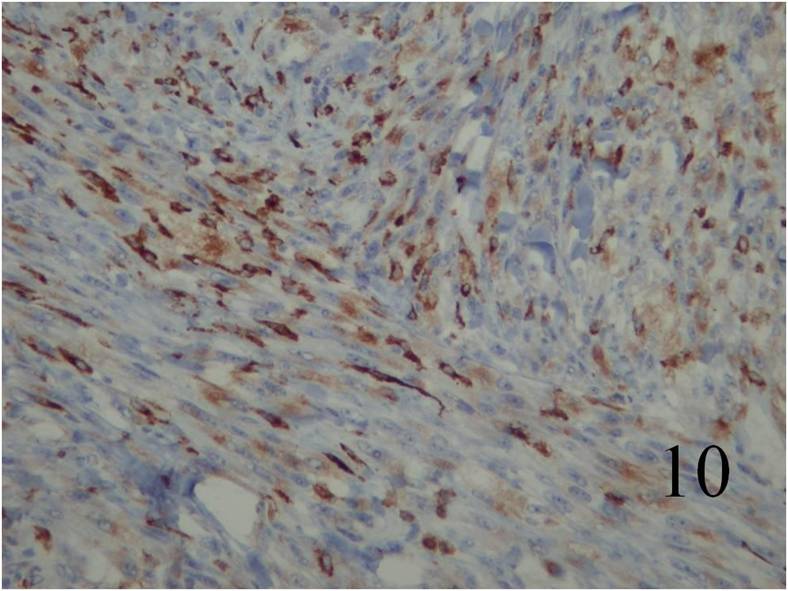

Fig. 7 Microscopic: Low and High (Fig. 8) power magnification of a leiomyosarcoma showing palisading spindle cells; with eosinophilic cytoplasm. Immunohistochemical stains for leiomyosarcoma are positive stain for actin (Fig. 9) and desmin (Fig. 10)

IMMUNOHISTOCHEMISTRY

Desmin and Actin are positive (Fig. 9,10 – above)